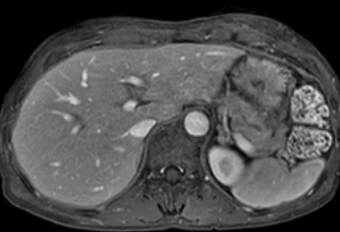

현재의 기술 발전으로 한 번 호흡 정지를 할 수 있는 시간(15-20초) 내에 MRI로 영상화할 수 있지만, 그 사이에 움직임이 발생하면 아래 그림과 같이 영상이 뿌옇게 되거나 물결치듯 보이게 되어 작은 간암의 경우 진단이 어려울 수 있습니다.

간 MRI 촬영 중 호흡 조절정도의 차이에 따른 영상의 질차이 왼쪽의 MRI는 촬영 중심한 호흡 운동으로 인해물결 모양의 허상이 심한 반면 오른쪽의 MRI는 촬영 중 호흡이정지가양호해영상이보다 깨끗하게 보입니다.